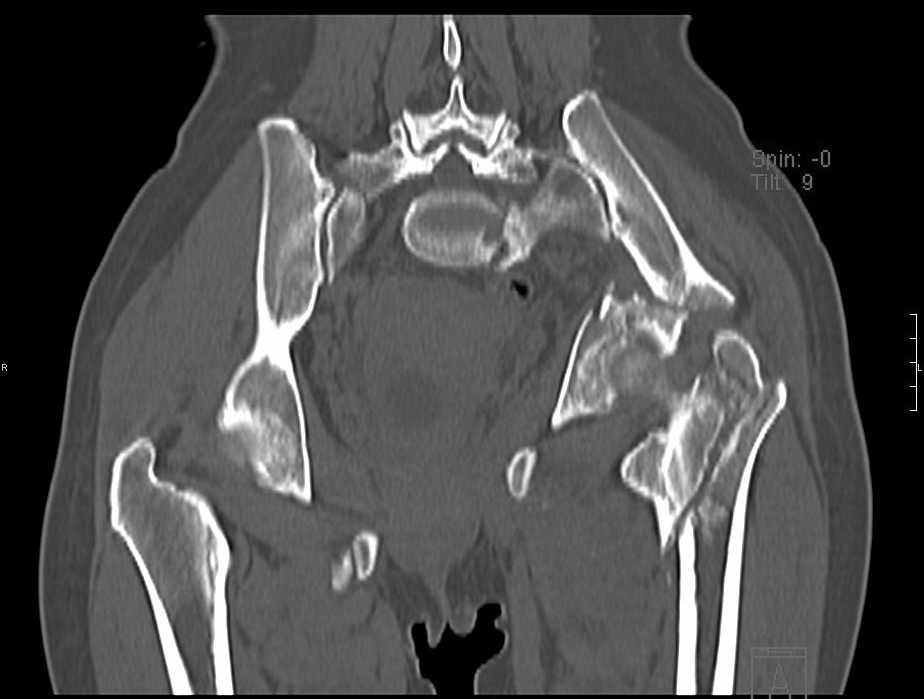

Больная 43 года (промышленный альпинист), 28.07.08 в результате падения с 5 этажа получила политравму: Перелом свода и основания черепа. Вертикально-нестабильное повреждение таза, осложнённое разрывом мочевого пузыря. Чрезвертельный перелом левого бедра. Перелом правой таранной кости, переломовывих правой кубовидной кости. Тупая травма живота, разрыв печени, ушиб почек. Забрюшинная гематома. В день травмы - лапаротомия, ушивание ран печени. Разрыв мочевого пузыря не диагностирован. Течение болезни осложнилось развитием мочевого затёка и обширной пред- и забрюшинной флегмоны, сформировался свищ мочевого пузыря. 19.8.2008 вскрытие, дренировние флегмоны, ревизия мочевого пузыря, обтурация мочевого свища (свищ закрылся в октябре), 1.10.2008 некрэктомия, пластика по Шеде-Лидскому правой кубовидной кости. По результатам КТ диагностирован рак правой почки (диагностическая находка), 8.10.2008 нефрэктомия справа. Переломы велись консервативно. Имеется вертикальное смещение левой половины таза с выраженным отведением крыла (клинически подвижности нет), несросшийся низкий двухколонный перелом левой вертлужной впадины с потерей конгруэнтности, укорочение около5 см, застарелый разрыв лонного сочленения, неправильно сросшиеся переломы обеих ветвей правой лонной кости с укорочением, патологическая подвижность лоно-седалищного фрагмента слева. Правая нижняя конечность неопорна, несмотря на то, что лежа прямую ногу поднимает, ходит на левой ноге (ортопедическая обувь) с костылями, справа тазобедренный ортез. Седалищные нервы работают.Урологи отпустили больную на 6 мес.

Извиняюсь, ошибся : опорная нога у больной правая. Левая нога неопорная, т.к. сращения на уровне бедра и вертлужной впадины нет.